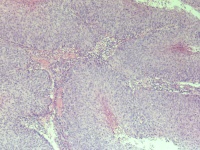

CINⅢ还是乳头状癌?

性别

女

年龄

73岁

临床诊断

宫颈癌

一般病史

阴道出血,宫颈口见菜花样组织

标本名称

宫颈组织

大体所见

1.5*1*0.5cm灰红碎组织

直接报鳞癌,手术后再定亚型(乳头状?疣性?浸润?),老头也要查查.

鳞状细胞癌

乳头状鳞癌。